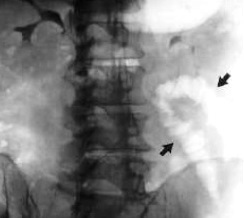

Qual o achado radiográfico característico da Isquemia Colônica?

“Sinal das impressões digitais”